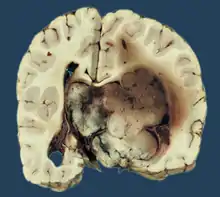

Choroid plexus papilloma, also known as papilloma of the choroid plexus, is a rare benign neuroepithelial intraventricular WHO grade I lesion found in the choroid plexus.[1] It leads to increased cerebrospinal fluid production, thus causing increased intracranial pressure and hydrocephalus.[2]

Choroid plexus papilloma occurs in the lateral ventricles of children and in the fourth ventricle of adults. This is unlike most other pediatric tumors and adult tumors, in which the locations of the tumors is reversed. In children, brain tumors are usually found in the infratentorial region and in adults, brain tumors are usually found in the supratentorial space. The relationship is reversed for choroid plexus papillomas.

CPPs are rare tumors of neuroectodermal origin. They make up 0.4 to 0.6 percent of all intracranial neoplasms in children and are the third most prevalent congenital brain tumors after teratomas and gliomas.[3] With a median age upon diagnosis of 3.5 years, this lesion is often a disease of infancy. They often reside supratentorial in the lateral ventricles of infants (most commonly in the atrium).[4] The fourth ventricle in adults is the optimum location.[5] Adults rarely have it at the cerebellopontine angle.[4]